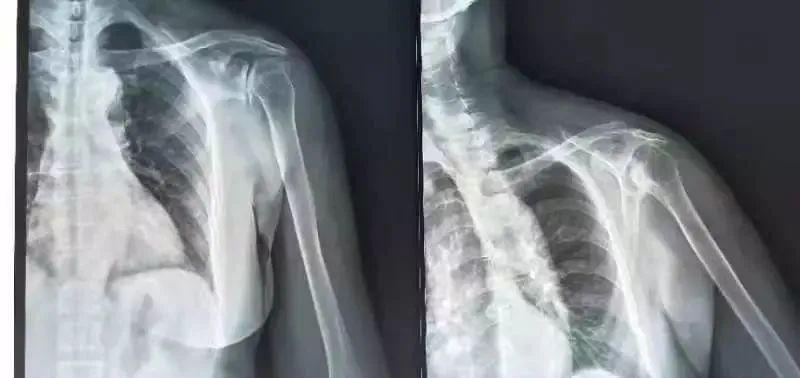

外伤,明显的外伤引起肩关节脱位、骨折等,一般较易诊断。